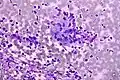

Micrograph of a Field stain showing malignant melanoma.